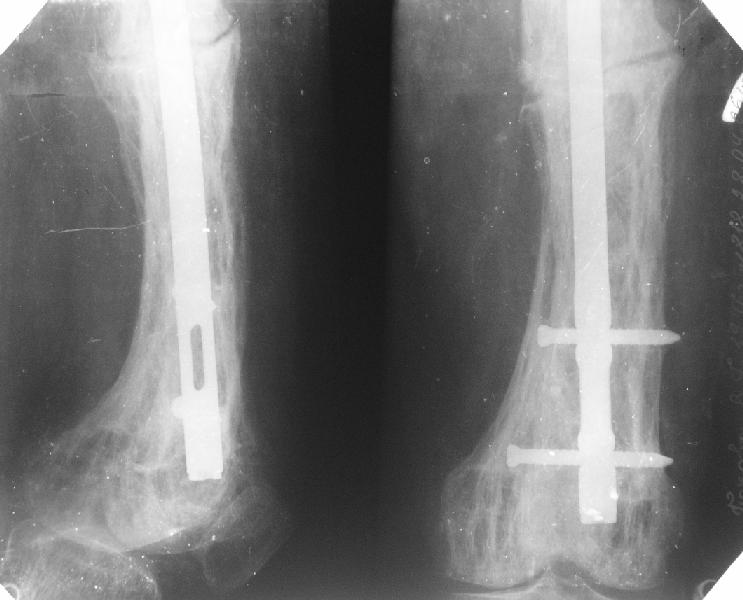

Пациент 82 лет, поступил через 5 мес. с несросшимся переломом после открытого интрамедуллярного остеосинтеза. Выполнили реостеосинтез стержнем 12 мм. ( мах. доступного нам в 2003 г.) Через 4 мес динамизация. В течении 2х лет сращения нет, тем не менее конечность опорна (ходит с тростью). От очередного реостеосинтеза отказались из-за сопутств. патологии.

PS: случай конечно не аналогичный, учитывая первичный открытый остеосинтез.